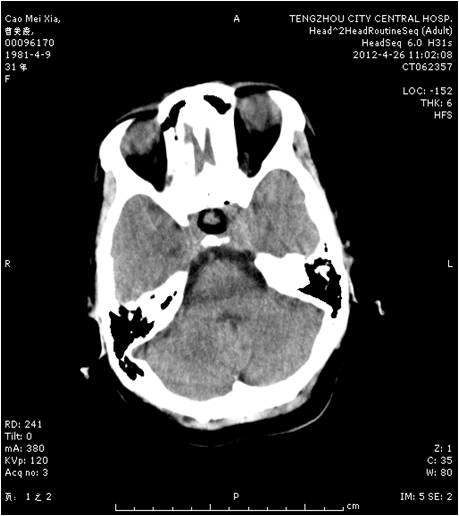

轉(zhuǎn)移瘤切除術(shù)前

轉(zhuǎn)移瘤切除術(shù)后